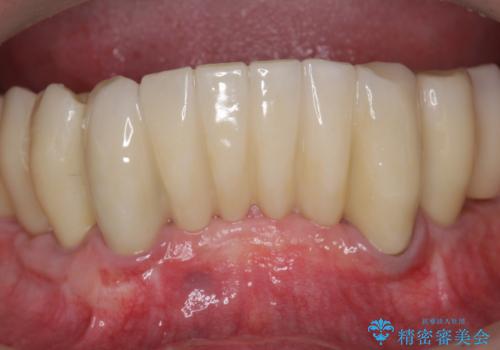

歯周外科で達成する、安定したクラウン周囲の歯肉環境

歯ぐきの腫れを改善する歯周外科手術を伴うセラミック治療